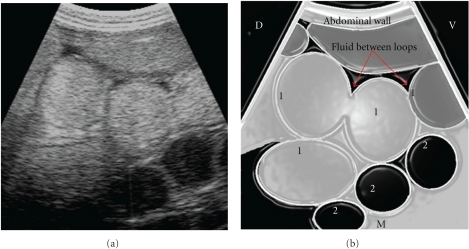

Small bowel obstruction with (1) dilated loops of bowel with hyperechoic contents contrasting (2) dilated loops of bowel with hypoechoic contents.